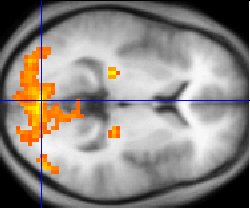

Monochrome fMRI image of a horizontal cross-section of a human brain. A few regions, mostly to the rear, are highlighted in orange and yellow.

Functional magnetic resonance imaging provides some evidence for both underconnectivity and mirror neuron theories.[56][57]

Asperger syndrome appears to result from developmental factors that affect many or all functional brain systems, as opposed to localized effects.[58] Although the specific underpinnings of AS or factors that distinguish it from other ASDs are unknown, and no clear pathology common to individuals with AS has emerged,[7] it is still possible that AS's mechanism is separate from other ASDs.[59] Neuroanatomical studies and the associations with teratogens strongly suggest that the mechanism includes alteration of brain development soon after conception.[54] Abnormal migration of embryonic cells during fetal development may affect the final structure and connectivity of the brain, resulting in alterations in the neural circuits that control thought and behavior.[60] Several theories of mechanism are available; none are likely to provide a complete explanation.[61]

The underconnectivity theory hypothesizes underfunctioning high-level neural connections and synchronization, along with an excess of low-level processes.[56] It maps well to general-processing theories such as weak central coherence theory, which hypothesizes that a limited ability to see the big picture underlies the central disturbance in ASD.[62] A related theory—enhanced perceptual functioning—focuses more on the superiority of locally oriented and perceptual operations in autistic individuals.[63]

The mirror neuron system (MNS) theory hypothesizes that alterations to the development of the MNS interfere with imitation and lead to Asperger's core feature of social impairment.[57][64] For example, one study found that activation is delayed in the core circuit for imitation in individuals with AS.[65] This theory maps well to social cognition theories like the theory of mind, which hypothesizes that autistic behavior arises from impairments in ascribing mental states to oneself and others;[66] or hyper-systemizing, which hypothesizes that autistic individuals can systematize internal operation to handle internal events but are less effective at empathizing when handling events generated by other agents.[67]